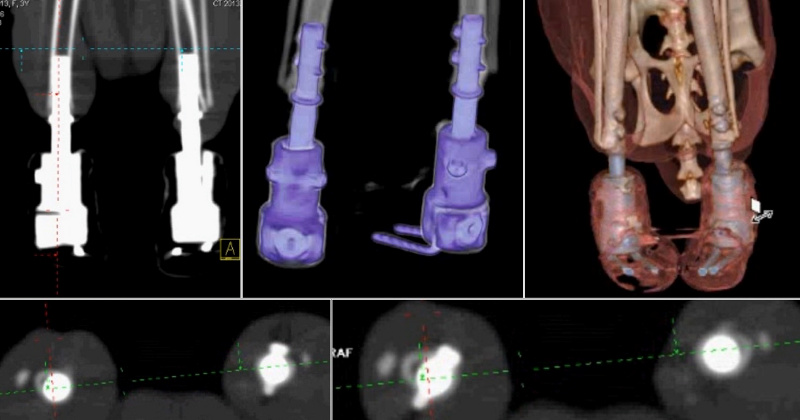

«У одного из котов отсутствовала передняя лапа, у другого — задняя. Их хозяева обратились в ветклинику, и врачи предложили им опробовать способ лечения с использованием имплантатов с нашим покрытием. Хозяева согласились, животных прооперировали. Сейчас оба они находятся под наблюдением, врачи-ветеринары систематически делают им рентген и томографию, результаты которых показывают, что имплантаты успешно прижились. Четвероногие пациенты, по словам врачей, чувствуют себя с искусственными «лапами» так же комфортно, как если бы это были их собственные», — цитирует пресс-служба Сергея Твердохлебова.

Компьютерная томограмма тазовых конечностей через три месяца после имплантации